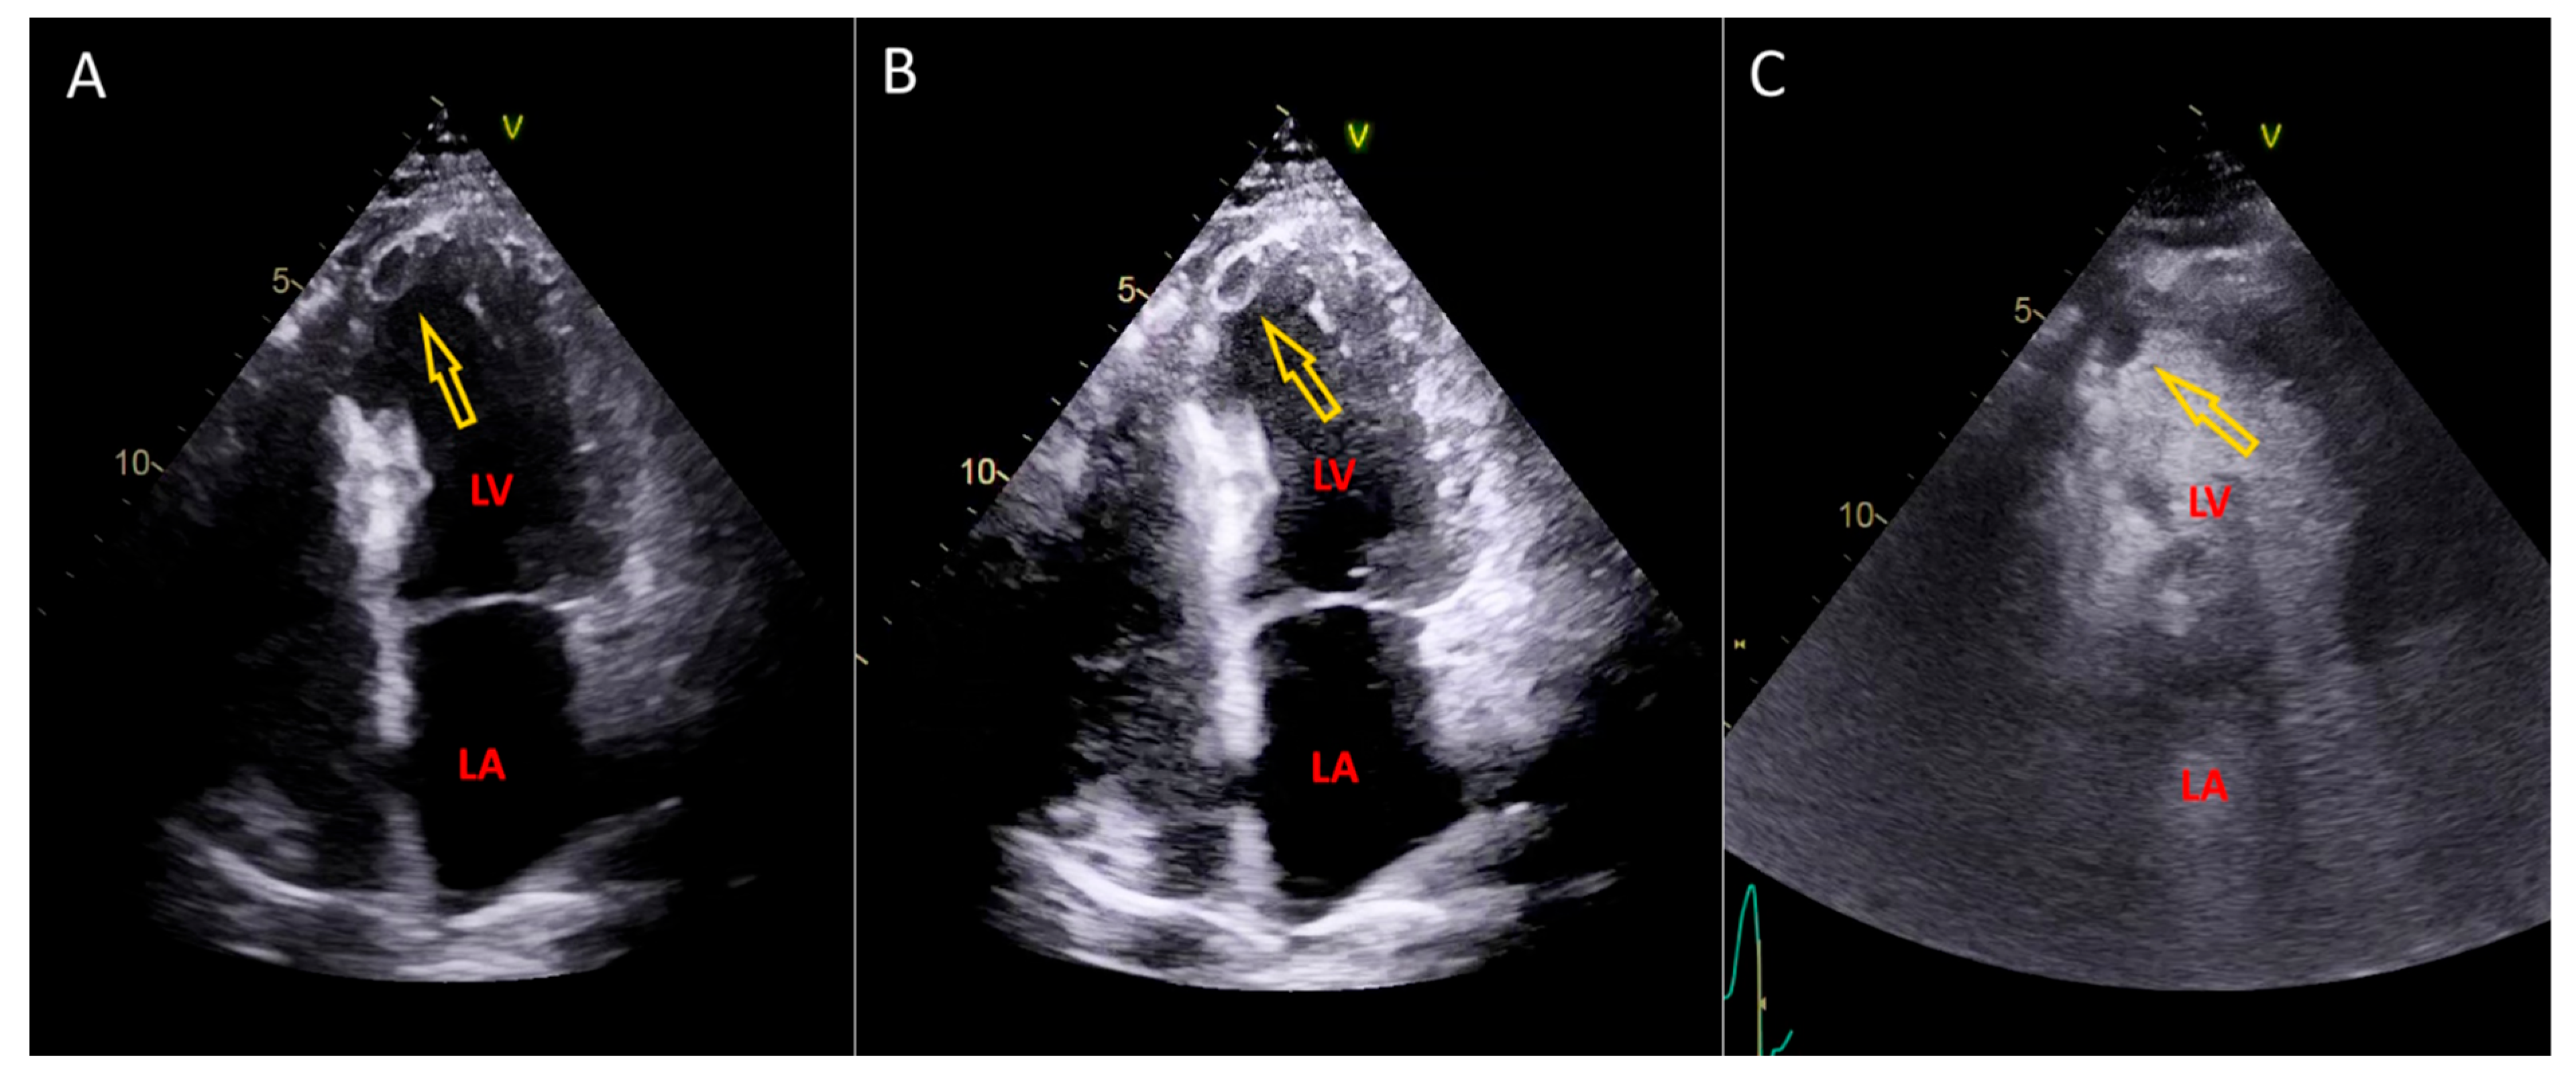

2.3. Why We Need Left Ventricular Thrombus Detection Method

2.4. Postprocessing: Left Ventricular Thrombus Detection Method

2.5. Simplified Explanation of the Left Ventricular Thrombus Detection Method (LVTDM)